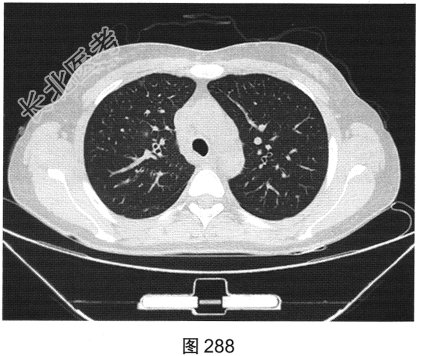

- [材料题] 患者女性,43岁,因“确诊肺低分化腺癌1周”就诊。患者于2014年11月无明显诱因出现咳嗽、咳痰,无胸闷胸痛,无咯血,无发热、乏力、体重减轻等。自服中药治疗,止咳效果尚可。2015年4月22日在山海关人民医院行胸部CT:显示①慢性支气管炎继发感染,建议结合临床及病史考虑;②右侧中间段支气管及中叶支气管壁增厚、管腔狭窄伴右肺中叶阻塞性肺不张,右侧肺门及纵隔多发淋巴结增大,建议增强扫描。后补做增强CT:右肺中叶支气管增厚,管腔狭窄伴阻塞性肺不张,考虑右侧中心型肺癌伴纵隔多发淋巴结增大,建议行支气管镜检查。支气管镜取活检病理:示低分化腺(右肺中叶)癌,建议做免疫组织化学检测,以进一步明确诊断。于北京肿瘤医院行PET/CT检查:①右肺中叶支气管起始部位高代谢结节,符合中心型肺癌表现;右肺中叶部位阻塞性不张,不张肺内高代谢结节,倾向肺内转移;双肺多发转移结节;双锁骨上区、左胸肌间、纵隔及双肺门多发淋巴结转移。②脑部未见明显高代谢征象,建议行增强MRI检查。③双叶甲状腺炎性或非特异性摄取,建议行B超及甲状腺功能检查。患者精神状态良好,体力、食欲、睡眠均正常,体重无明显变化,大便、排尿正常,为进一步检查及治疗,门诊以“肺癌”收入院。2015年5月5日在我院行CT检查,如图288~图295所示。